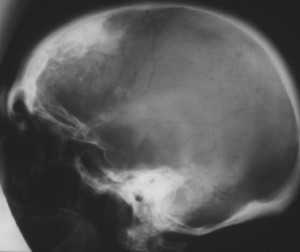

Диагноз ставят на основе жалоб и клинической картины; также используют гистологические методы исследования. На рентгенограмме визуализируется утолщение лобной кости. Синдром Морганьи — Стюарта — Мореля дифференцируют в первую очередь от болезни Иценко — Кушинга и адипозогенитальной дистрофии.

Основным проявлением синдрома М.С.М., без которого он не существует как таковой, является утолщение внутренней пластинки лобной кости (гиперостоз). Это своеобразное разрастание гиперплазированной костной ткани, хорошо распознаваемое рентгенологически и не определяемое при осмотре и пальпации. Явление это довольно распространенное, но в большинстве случаев не проявляется клинически и является рентгенологической находкой [18, 34, 35].

Рентгенологически определяются костные разрастания на поверхности внутренней пластинки лобной кости; они могут быть довольно ограниченными или занимать обширные участки. Иногда они диффузно распространяются на свод черепа, реже - на его основание.

Рентгенограмма черепа (боковая проекция) больного с синдромом Морганьи: резкое утолщение лобной кости (указано стрелкой) за счет гиперостоза внутренней пластинки.

Диагноз устанавливают на основании клин, картины и данных ЭЭГ. Для уточнения диагноза необходимо рентгенол, исследование, т. к. гиперостоз внутренней пластинки лобной кости (рис.), являющийся обязательным признаком этого синдрома, может быть выявлен только при краниографии (см.). О локализации и протяженности изменений судят по снимкам черепа в боковой проекции. Как правило, дополнительные костные разрастания в виде отдельных узлов или разлитого характера располагаются в средней и нижней третях чешуи лобной кости, изредка — и в теменных костях. По сравнению с неизмененными участками кость может быть утолщена в 2—3 раза. Этим изменениям могут сопутствовать различной формы и размеров очаги обызвествления твердой мозговой оболочки в зоне, примыкающей к внутренней поверхности лобной кости.

При длительном течении заболевания и резко выраженном гиперостозе лобной кости из-за уменьшения объема черепа на краниограммах могут быть обнаружены признаки повышения внутричерепного давления (усиление пальцевых вдавлений, углубление борозд синусов и др.).